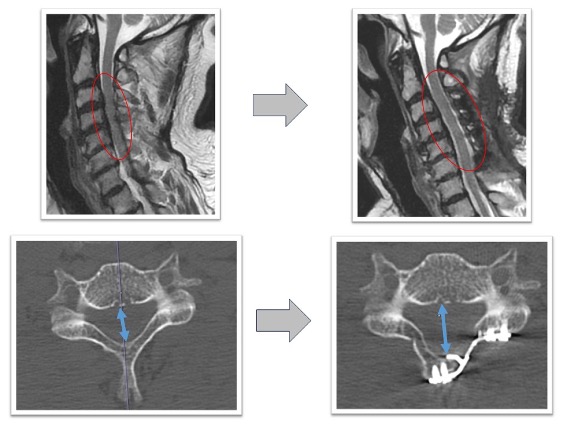

頚椎椎弓形成術実例(*患者様の許可を得て掲載しています)

頚椎症性脊髄症

上肢の運動障害、歩行障害の患者様に対して頚椎椎弓形成術を実施。術後MRI画像で頚髄の圧迫が解除され頚髄前後にスペースが生まれています(図赤丸)。また、CT画像では術前後の比較で脊柱管の前後幅が約1.5倍以上に拡大していることが確認できます(図青矢印)。術後は歩行安定し、上肢運動も改善しています。